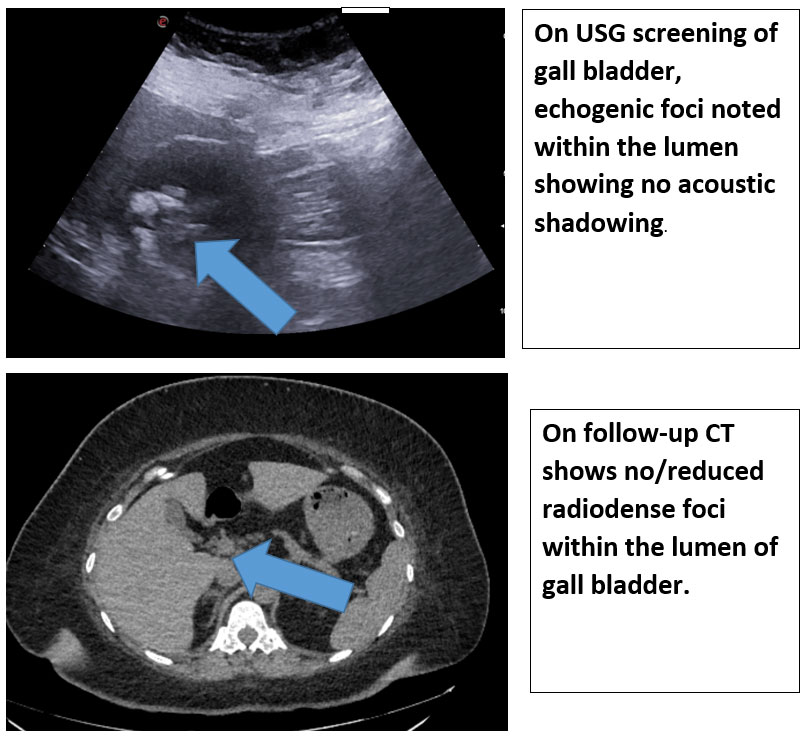

Ultrasound:

• Echogenic sludge or calculi-like material.

• May or may not produce posterior acoustic shadowing.

CT may demonstrable hyperdense material within the gall bladder due to calcium content.

Unlike true gallstones, these deposits resolve completely after discontinuation of the drug, which serves as the most important diagnostic clue.